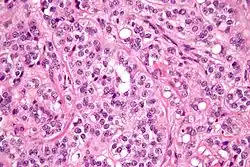

High magnification micrograph of a Leydig cell tumour. H&E stain.

High magnification micrograph of a Leydig cell tumour. H&E stain. -